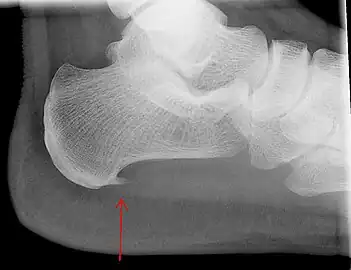

An incidental finding associated with this condition is a heel spur, a small bony calcification on the calcaneus (heel bone), which can be found in up to 50% of those with plantar fasciitis.[6] In such cases, it is the underlying plantar fasciitis that produces the heel pain, and not the spur itself.[13] The condition is responsible for the creation of the spur though the clinical significance of heel spurs in plantar fasciitis remains unclear.[12]

Heel bone with heel spur

Medical imaging is not routinely needed. It is expensive and does not typically change how plantar fasciitis is managed.[15] When the diagnosis is not clinically apparent, lateral view X-rays of the ankle are the recommended imaging modality to assess for other causes of heel pain, such as stress fractures or bone spur development.[7]